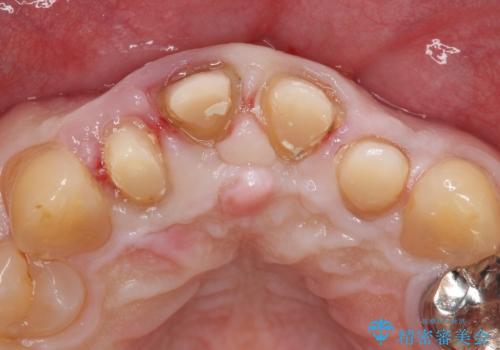

- 前歯の見た目が気になるといらっしゃった方の症例です。

再根管治療後、オールセラミッククラウンによる補綴を行いました。

右上2は歯茎のラインを整えるため歯周外科を行っております。

- オールセラミッククラウン…¥100,000×4、仮歯…¥10,000×4、ファイバーコア…¥20,000×4、歯周外科…¥100,000、精密根管治療費別途費用は治療当時の料金となります